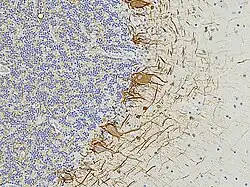

A formalin-fixed and paraffin-embedded section of the human cerebellum is stained with an antibody specific to NF-L, visualized with a brown dye. Cell nuclei are counterstained with a blue dye. The nucleus-rich region on the left side corresponds to the granular layer, while the region on the right represents the molecular layer. The antibody binds to the processes of basket cells, the parallel fiber axons, the perikarya (cell bodies) of Purkinje cells, and various other axons.

In histological sections of human brain tissue, NF-L can also be visualized using immunostaining. For example, in formalin-fixed and paraffin-embedded sections of the human cerebellum, an antibody specific to NF-L reveals its presence throughout various neuronal compartments[7]. The brown-stained antibody binding highlights the axonal processes of basket cells, the parallel fibers of granule cells,[21][18] the perikarya of Purkinje cells,[21] and other axonal elements. Counterstaining with a blue dye allows for the visualization of cell nuclei, delineating the granular layer on the left side of the section and the molecular layer on the right.[21] These staining patterns underscore the widespread and structurally critical role of NF-L in both developing and mature neurons.[19][18]